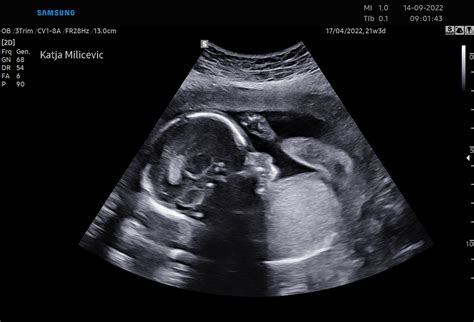

V dvanajstem tednu nosečnosti dojenček doseže velikost približno 12 do 14 gramov in meri okoli pet centimetrov. Njegove oči, ki so se do sedaj že popolnoma izoblikovale, se premikajo proti končnemu položaju. Dojenček že lahko odpre svoja usteca in premika prstke na rokah in nogah, kar kaže na nadaljnji razvoj motoričnih sposobnosti.

Možgani se vse bolj hitro razvijajo; zarodne živčne celice se hitro razmnožujejo, sinapse pa že pošiljajo signale. Do tega tedna so se povsem izoblikovali že vsi njegovi organi in telesni sistemi. Srček pridno črpa kri, medtem ko se dojenček premika ne le refleksno, temveč tudi spontano in naključno. Ti gibi so sicer še tako drobni, da jih nosečnica še ne more občutiti. V tem tednu plod že pije plodovnico in jo izloča nazaj v svoje okolje. Ker je plodovnica sterilna, ni nevarnosti, da bi se mu kaj zgodilo. Plodovnica je neverjetna tekočina, ki se popolnoma obnovi v samo treh urah, pri čemer je delno sestavljena iz plodovega urina.

V tem tednu se že začenja izločati žolč, ledvica pa proizvajati urin. Plod je zmožen premikanja in refleksnih gibov, deluje pa tudi peristaltika črevesja. Plodu že rastejo nohti in lasje. Velikost med 5 in 6 centimetrov ter teža okoli 14 gramov sta tipični. Srček bije s 160 udarci na minuto. Vsi ti procesi predstavljajo pripravo zarodka na življenje izven maternice.